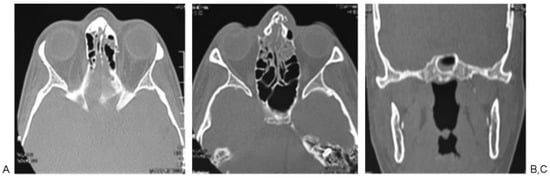

According to Manson’s classification, 17.9% (n ¼ 38) of the trauma in the group corresponded to high-energy trauma, followed by medium-energy trauma at 33.5% (n ¼ 71) and low-energy trauma at 48.6% (n ¼ 103). Among the patients with high-energy trauma, 31.5% (n ¼ 12) had combined fractures of the sphenoid bone and sphenoid sinus and 31.5% (n ¼ 12) had sphenoid sinus fractures only. In contrast, 1.4% (n ¼ 3) of patients with middle-energy trauma had sphenoid bone fractures, 5.6% (n ¼ 4) of the patients had sphenoid sinus fractures, and 4.2% (n ¼ 3) of the patients had sphenoid bone and sphenoid sinus fractures. In the low-energy trauma group, only 1 patient presented sphenoid sinus fracture (0.97%; Table 3; Figure 2, Figure 3 and Figure 4).

Figure 2. Patient 1: high-energy trauma and panfacial fractures. (A) Zygomatic arch, malar, and upper jaw fractures. (B) Sphenoid sinus fracture. (C) Computed tomography three-dimensional reconstruction showing the fractures at the middle third and jaw.